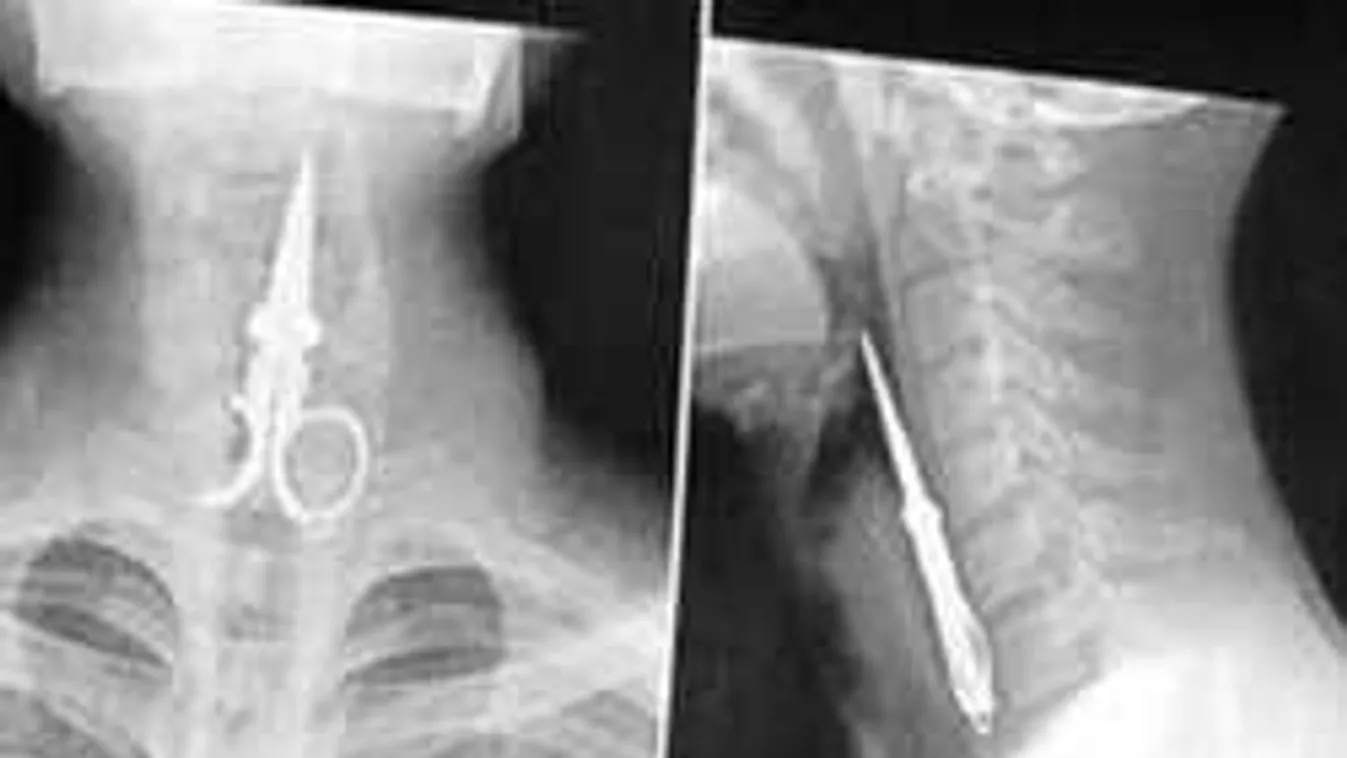

ÉLETMÓDI 2017. 03. 18. Elképesztő tárgyak az emberi testben: Sokkoló röntgenfelvételek! +18 Talán gyerekkorodban te is nyeltél le gombot. Vagy egy darabot a legóból. De most nem fogsz hinni a szemednek.